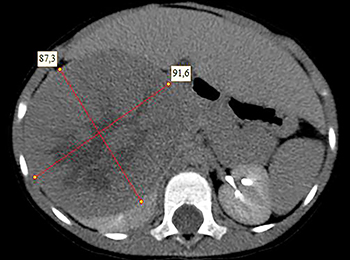

Рисунок 1. КТ брюшной полости ребенка с большой нефробластомой с метастазами в печень.

Рисунок 2. КТ: опухоль при поступлении.Клинически: при пальпации опухоль в проекции правой почки до 12 см в диаметре. Общеклинические исследования в пределах возрастной нормы. При КТ органов брюшной и грудной полости: КТ-картина объемного образования правой почки без признаков интрапульмональных метастазов (см. рис. 2). УЗИ брюшной полости: в проекции правой почки солидно-кистозное образование 101ґ114ґ99 мм, объемом 500 мл, васкуляризация активная, интактная часть почки 57ґ12ґ40 мм. Объемное образование правой почки — опухоль Вильмса. Предварительный диагноз: опухоль Вильмса правой почки, 2-я стадия.